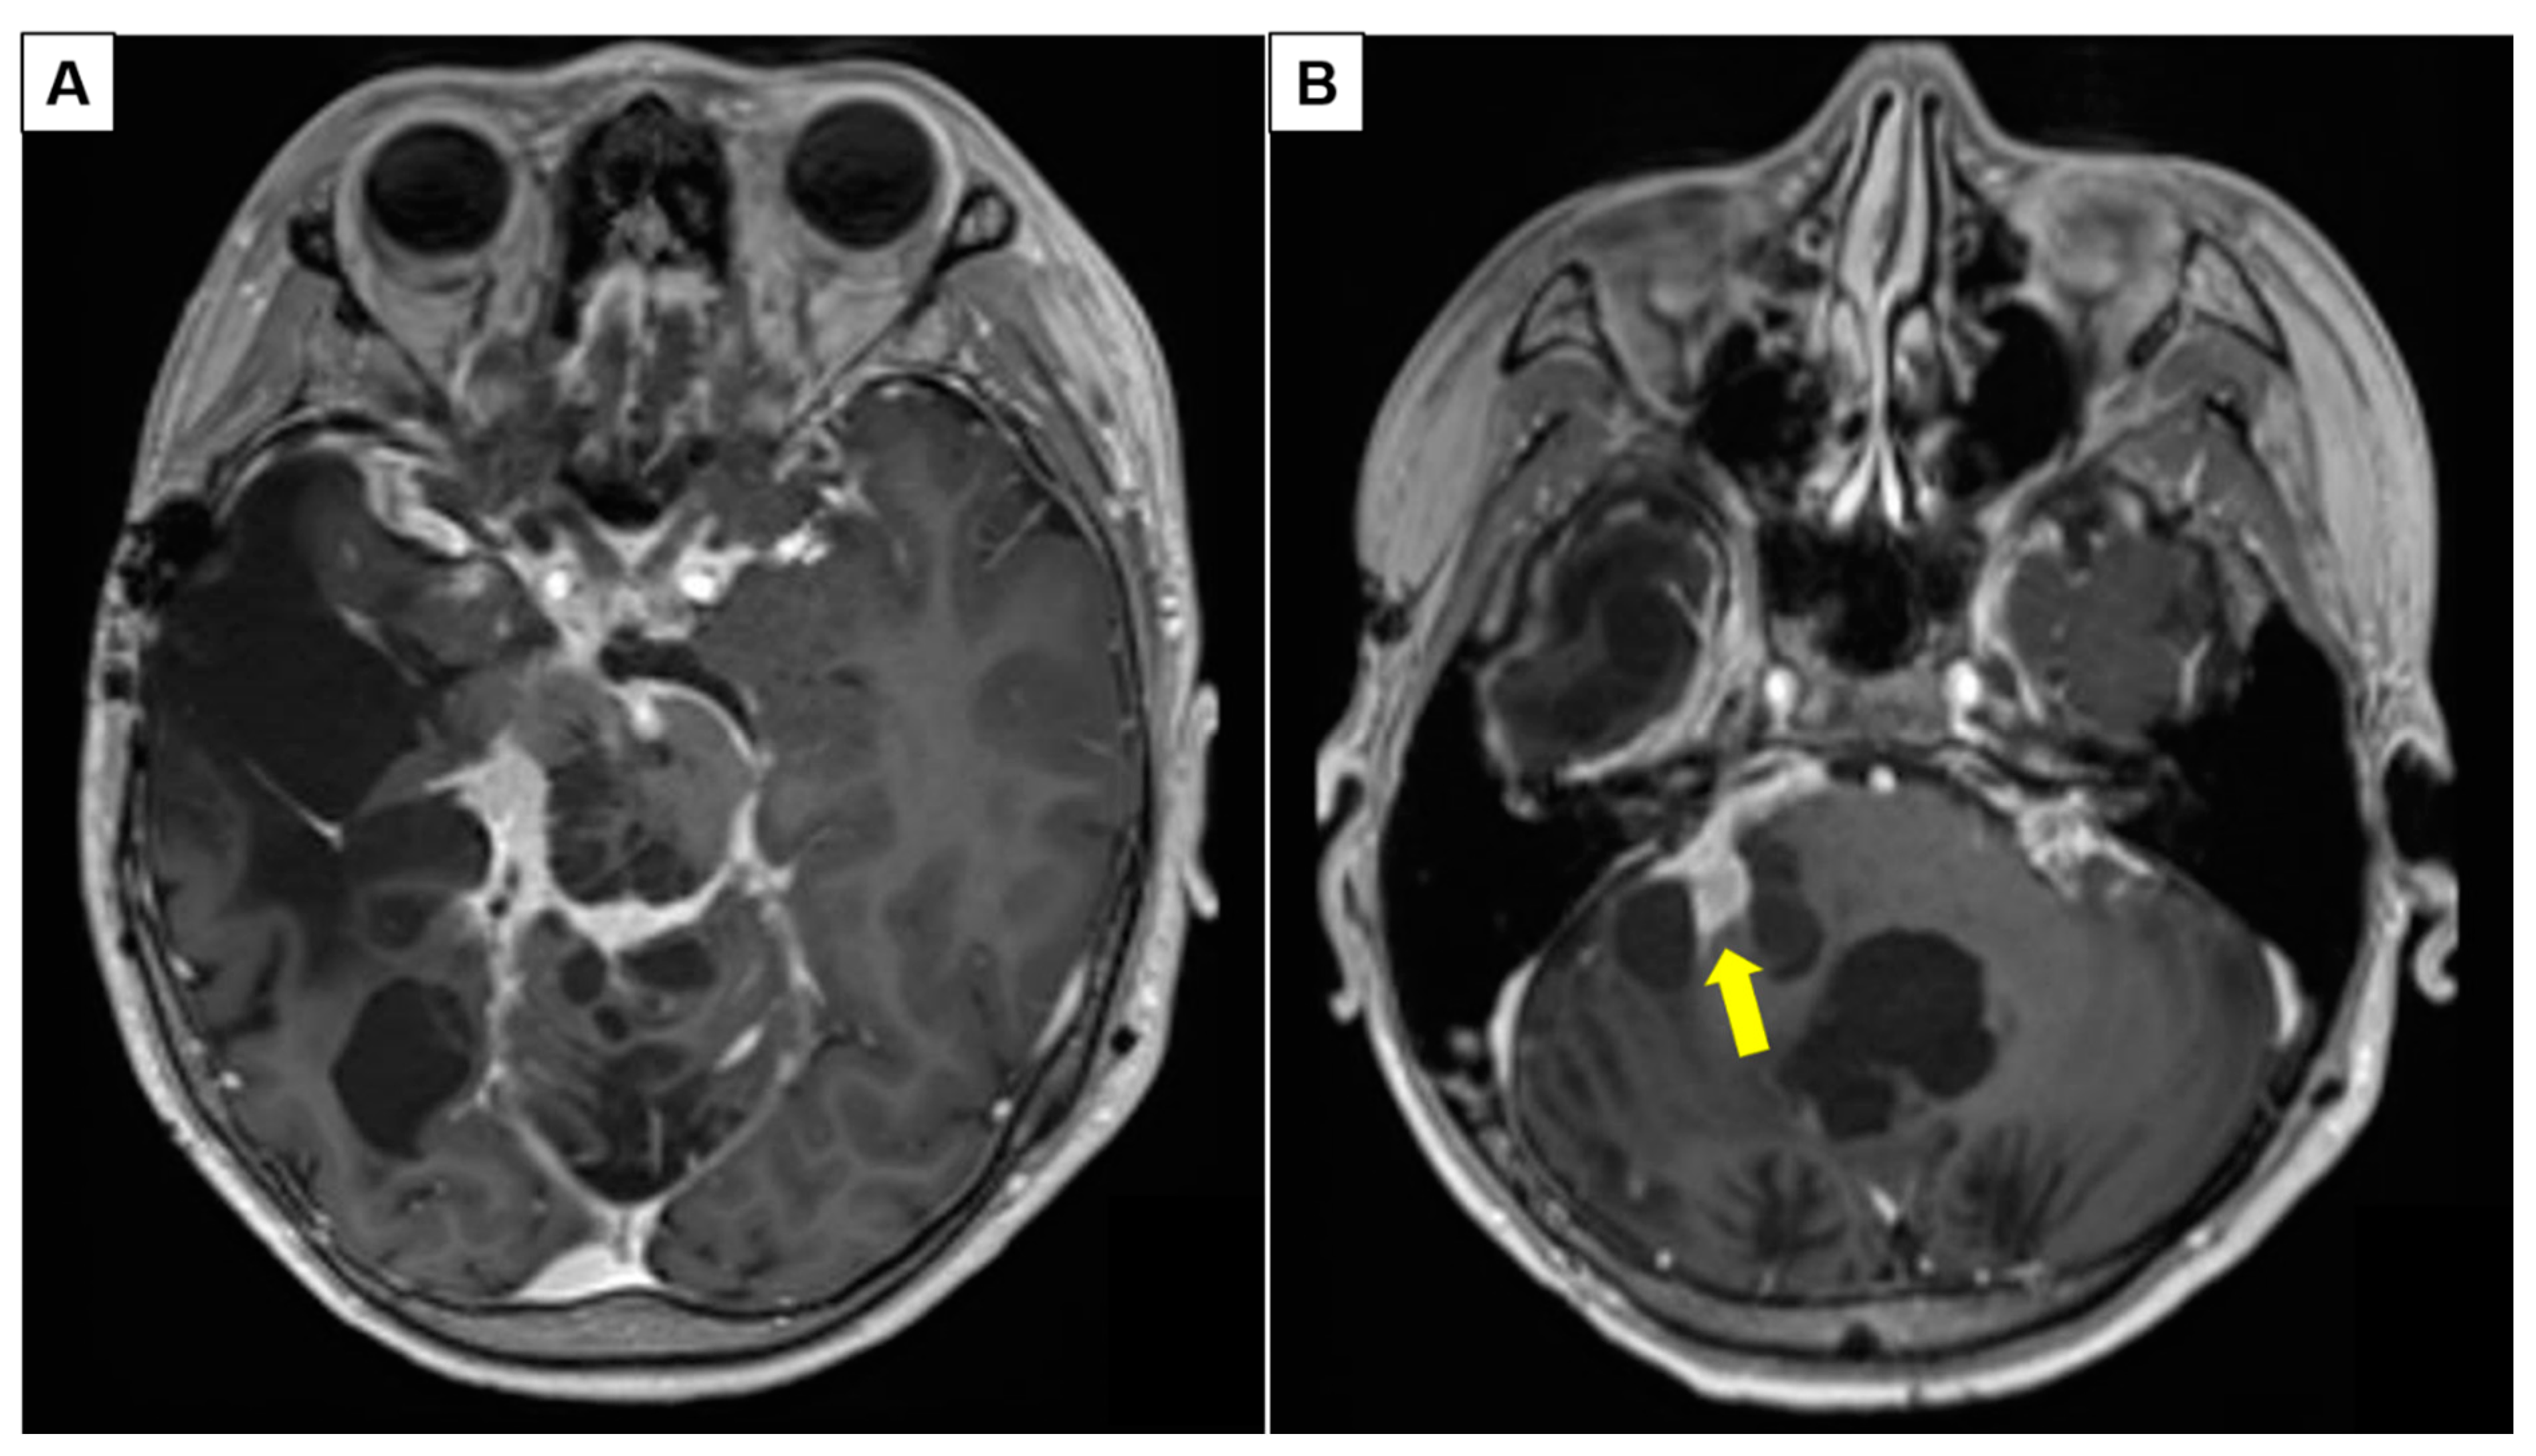

3.1.1. Patient 2: Large Frontotemporal PCA with Intratumoral Arterio-Venous Shunting

3.1.2. Patient 5: Progressive Intraventricular PCA with Leptomeningeal Disease